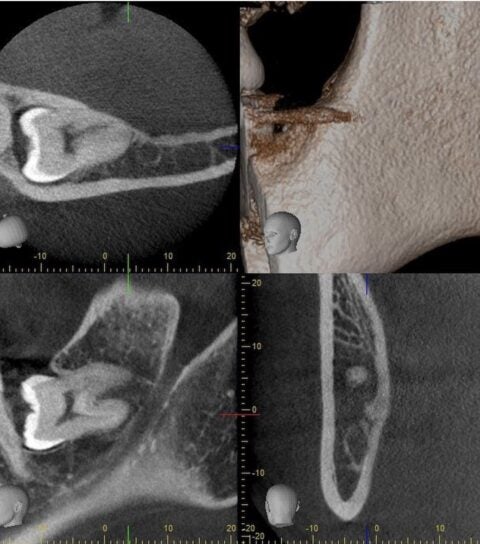

■親知らずが横向きに生えていたり、根っこの部分が神経に近い等、当院で安全に抜歯を行うことが可能でございます。

(※必要に応じて、当院に完備しておりますCT撮影をする場合もございます。)

■他院でお断りされた横向きの親知らずの抜歯も当院では無痛リラクゼーション治療で寝ている間にお痛みや音を感じることなく施術することが出来ます。(※ごく稀に神経に癒着しているようなクリニックレベルで非常に困難な物のみ提携大学病院へ紹介する場合があります。)